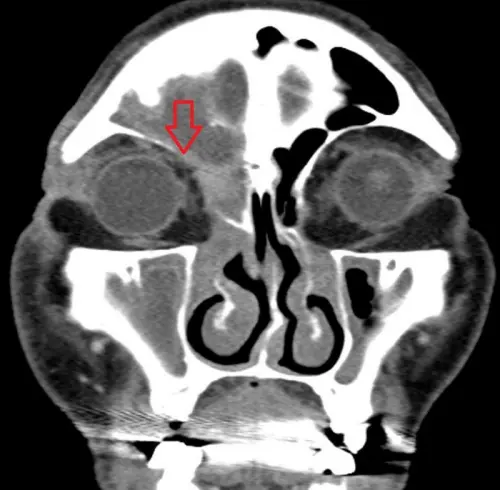

▲電腦斷層檢查顯示,李爺爺鼻竇阻塞,與眼周邊界模糊。(圖/台北慈院提供) 對於李爺爺病情,吳姳萱則說,影像檢查顯示鼻竇開口阻塞,膿液影響至眼周,導致上眼皮膿瘍,若採傳統手術,須翻開上唇、切開骨頭,出血較多且傷口大,恢復也較慢;先進手術則會使用3D導航,先確認病灶,再利用微創鼻竇內視鏡與削切刀清除發炎組織膿瘍,既能保持手術視野清晰,也可減少對正常組織的破壞,患者復原更快。